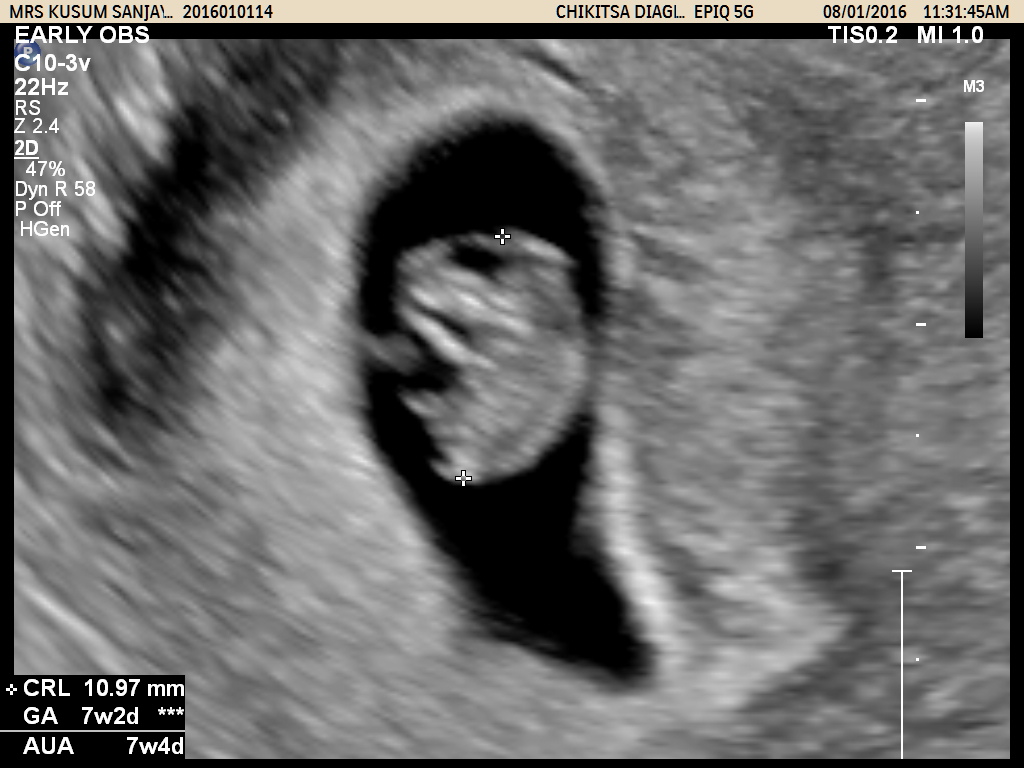

During the First Trimster Screening (Nuchal translucency, Nasal bone, etc)(11-13 weeks), the Anomalies Scan / Targetted Scan (20-24 weeks) we routinely examine the fetal heart and connecting blood vessels.

Specialist fetal heart scans at our Centre are carried out by Expert Team of Doctors. The scans are usually performed at 18-23 weeks gestation, but can be undertaken from as early as 13 weeks if necessary. If an abnormality is found, a detailed explanation of the problem and the outlook for the baby will be provided to the parents and a plan for the subsequent management of the pregnancy will be discussed.